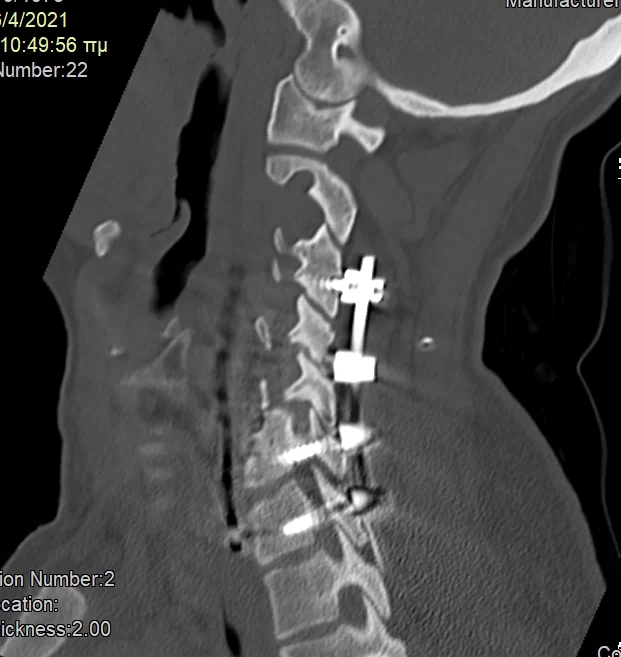

Διενεργήθηκε αρχικά οπίσθια σπονδυλοδεσία με διαυχενικές βίδες Α4, βίδες στα πλάγια ογκώματα Α5 και διαυχενικές βίδες Α7 και Θ1 ενώ έγινε και τρηματεκτομή Α6/7 δεξιά.

Στη συνέχεια, αφαίρεση της πρόσθιας πλάκας, ολοκλήρωση της σωματεκτομής Α5 & Α6, απελευθέρωση του νωτιαίου μυελου, πρόσθια δισκεκτομή Α7/Θ1 και τοποθέτηση πρόσθιας πλάκας Α4-Θ1.

Αρχικά έγινε οπίσθια σπονδυλοδεσία προκειμένω να στηριχθεί ο αυχένας της ασθενούς και να μειωθούν τα άλγη τα οποία οφείλονταν στην “αστάθεια” της αυχενικής μοίρας. Παράλληλα, διενεργήσαμε και οπίσθια τρηματεκτομή ώστε να εξασφαλίσουμε την απελευθέρωση της δεξιάς Α7 ρίζας, η οποία δημιουργούσε πόνο στην ασθενή. Όπως φαίνεται στη μετεγχειρητική αξονική τομογραφία, οι βίδες στους αυχένες του Α4 σπονδύλου τοποθετήθηκαν με ακρίβεια χιλιοστού. Σ’ αυτό, σημαντική ήταν η βοήθεια του διεγχειρητικού νευροπλοηγού σπονδυλικής στήλης με το πιο σύγχρονο σύστημα απεικόνισης (Ο-arm II)

Στη συνέχεια γυρίσαμε την ασθενή σε ύπτια θέση και αφού αφαιρέσαμε την παλαιά πλάκα, αποκαθηλώνοντας τον οισοφάγο, ολοκληρώσαμε τη σωματεκτομή και απελευθερώσαμε τα νευρικά στοιχεία και από μπροστά. Μια και δεν ήταν δυνατή η στήριξη της πλάκας στον Α7, αλλά ούτε και θέλαμε να καταλήξουμε ένα τεράστιο χάσμα, αποφασίσαμε να διατηρήσουμε τον Α7 και να διενεργήσουμε πρόσθια δισκεκτομή Α7/Θ1, καθηλώνοντας τελικά την πλάκα στον Α4, Α7 και Θ1 σπόνδυλο.